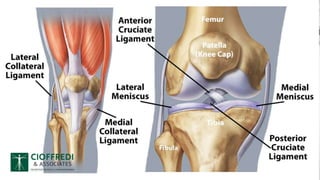

ANATOMY OF KNEE JOINT

LIGAMENTS

Two major ligaments (inside knee joint)

-Anterior and posterior cruciate ligament

Two other ligament (outside knee joint)

-Medial and lateral collateral ligament

-They act to stabilise knee sideways motion.

MENISCI

• Meniscus are C-shaped

fibrocartilaginous structures.

• Two in number

• Medial and lateral meniscus

• They act as shock absorbers

and also help in spreading

weight.